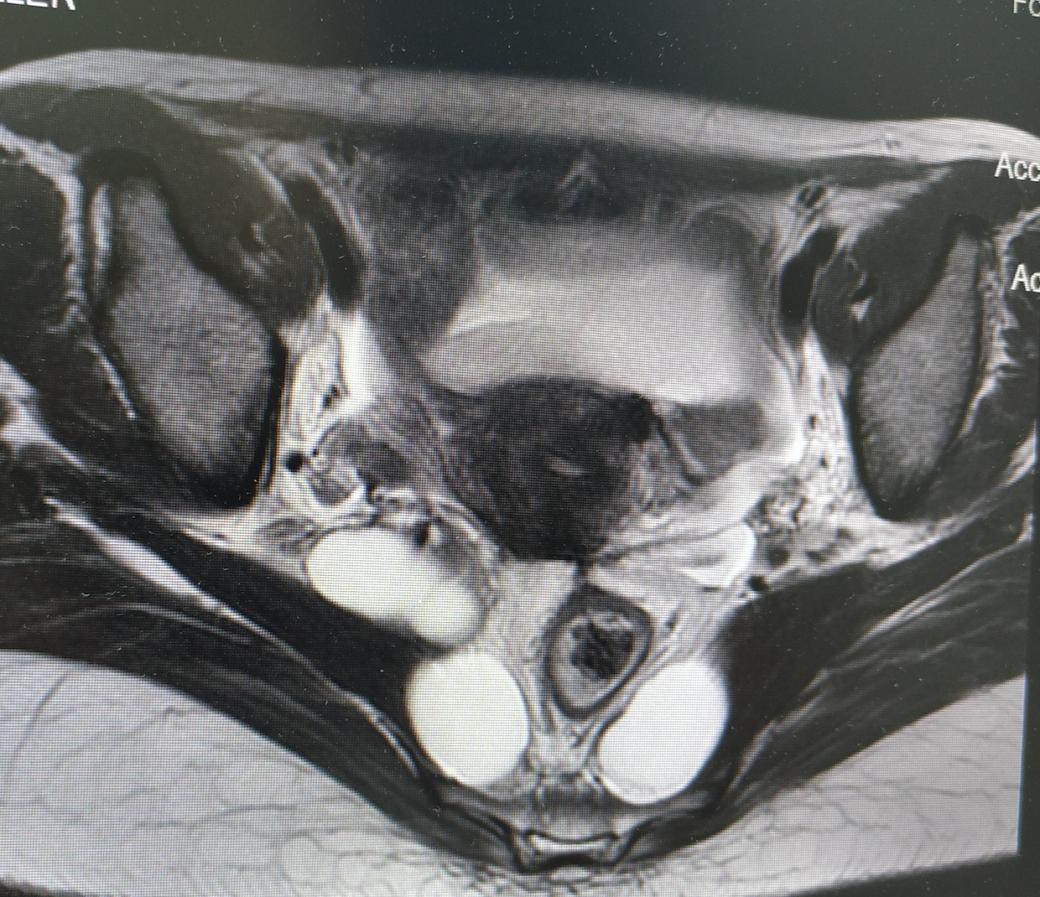

盆腔MR结果提示:

1、骶管、双侧骶椎间孔、骶骨及梨状肌前方盆腔内多发囊状信号影,考虑神经根袖囊肿,建议进一步检查;

2、右侧髋臼异常信号影,考虑血管瘤可能性大;

3、双侧腹股沟浅区小淋巴结显示。

神经外科会诊意见:患者查MR提示骶管、双侧骶椎间孔、骶骨及梨状肌前方盆腔内多发囊状信号影,考虑神经根袖囊肿。患者现无相关神经压迫等症状,建议定期复查,暂不考虑手术治疗。